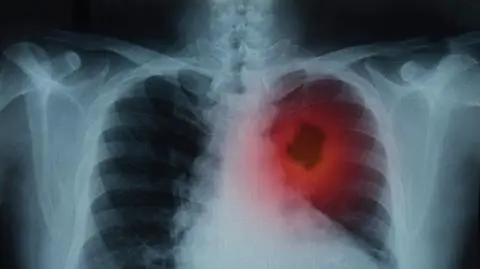

Naukowcy z Wielkiej Brytanii odkryli mechanizm, w jaki sposób zanieczyszczenie powietrza wywołuje choroby nowotworowe u osób niepalących. Za powstawanie szkodliwych mutacji odpowiedzialne są zawieszone cząsteczki PM2,5, powodujące miejscowe zapalenia w tkankach płuc. Co istotne, wyniki badań pokazały również, że mechanizm powstawania nowotworów może zostać zahamowany.

Zanieczyszczenie powietrza wpływa na zapadalność na wiele poważnych chorób, w tym astmę, choroby serca i demencję. Jest ono także powiązane z występowaniem raka płuc - w 2019 roku na świecie zmarło około 300 tysięcy osób, u których występowanie nowotworu przypisano narażeniu na pyły PM2,5. Mechanizm powstawania raka płuc u osób, które nigdy nie paliły, pozostawał jednak do tej pory tajemnicą.

Naukowcy z University College London i Instytutu Francisa Cricka przyjrzeli się danym medycznym zebranym od ponad 400 tysięcy ludzi z Wielkiej Brytanii, Korei Południowej i Tajwanu. Niezależnie od części świata wśród osób zamieszkujących obszary z wysokim stężeniem pyłów zawieszonych (PM2,5) w powietrzu stwierdzono częstsze występowanie chorób nowotworowych, w tym tych powiązanych z mutacją genu EGFR, szczególnie często występującą u niepalących chorych.

Wyniki te nie były niespodzianką - związek pomiędzy mikropyłami a zwiększoną zapadalnością na raka płuc jest znany już od wielu lat. Spory problem dla naukowców stanowiło natomiast wyjaśnienie tego mechanizmu. Do tej pory nie udało się znaleźć dowodów na to, że zanieczyszczenia powietrza bezpośrednio wywołują mutacje kodu DNA, a co za tym idzie - nowotwory płuc.

Jak tłumaczy Charles Swanton z Instytutu Francisa Cricka, główna hipoteza dotycząca wpływu PM2,5 na komórki płuc głosi, że mikropyły powodują tam lokalne stany zapalne. Zapalenie budzi nieaktywne komórki przenoszące mutację EGFR, które pojawiają się w tkankach wraz z wiekiem. Połączenie tych dwóch czynników może spowodować niekontrolowany wzrost komórek, przyczyniając się do tworzenia guzów.